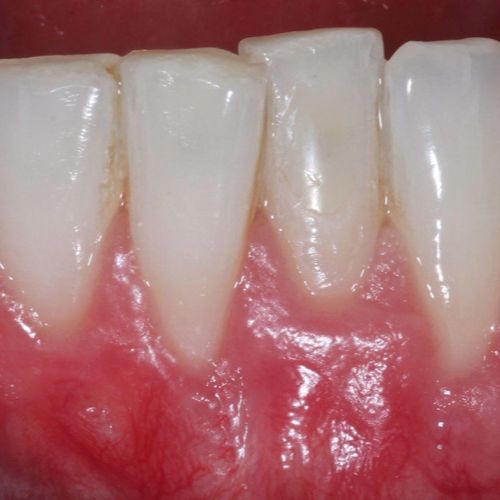

![]() | ![]() |

| Free gingival graft surgery’ to thicken gum and prevent further recession | Gum recession surgery in an aesthetic site |